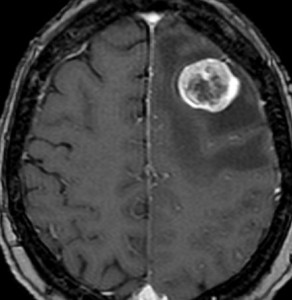

- MRIで転移性脳腫瘍は,低信号から高信号を示すものまでいろいろです

- ガドリニウム造影剤で増強されてくっきり写ります

- 腫瘍中心壊死のためリング状に増強されると膠芽腫との鑑別が難しいことがあります

- 周辺脳浮腫(腫瘍の周囲の脳が腫れている)が特徴です

典型的な転移性脳腫瘍(単発)のMRI

腺癌の左前頭葉転移です。左のガドリニウム造影剤を使った画像では腫瘍が白く写っています。腫瘍の内部が一部壊死しているので黒っぽく見えます。右はフレア画像です。腫瘍の周囲の脳が腫れて脳浮腫(白く滲むようなところ)を生じています。

開頭手術で摘出した半年後の画像です。腫瘍は再発していなくて,脳の腫れも引いています。転移が発見された時には,見当識障害などの左前頭葉症状が強かったし,摘出がとても簡単な場所だったので手術しました。線状皮膚切開・小開頭ですから1時間くらいの簡単な手術です。でも,26mmくらいでしたから,定位放射線治療も可能なものでした。この患者さんは幸いなことに半年で再発していませんが,開頭手術による摘出だけだと同じ場所からまた再発することもあり,それから放射線治療を加えなくてはならないこともあります。個々の判断は難しいのですが,基本的には開頭手術より定位放射線治療のほうがいいと考えて下さい。